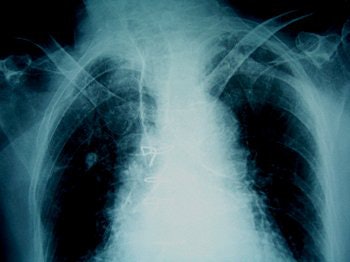

| If the frontal sinuses (above) of an unidentified corpse are intact, they can be as distinctive as fingerprints. Bone spurs (below) can also be unique identifying markers, as these two example x-rays show. Images courtesy of Nancy Adams. |

Adams offered some details on how forensics experts apply imaging to body identification. Frontal sinuses "can be as unique as fingerprints," she said. "You also do the feet. There will be bone spurs on the heels. Another thing is the legs. One individual had a total knee replacement."

In one case, the x-ray showed a distinctive femoral callous formation indicating that "the patient had had orthopedic surgery and some type of prosthesis involving screws or a compression plate, and there was a tiny piece of metal still left in the fracture site. (That would be) a positive way to identify that body."